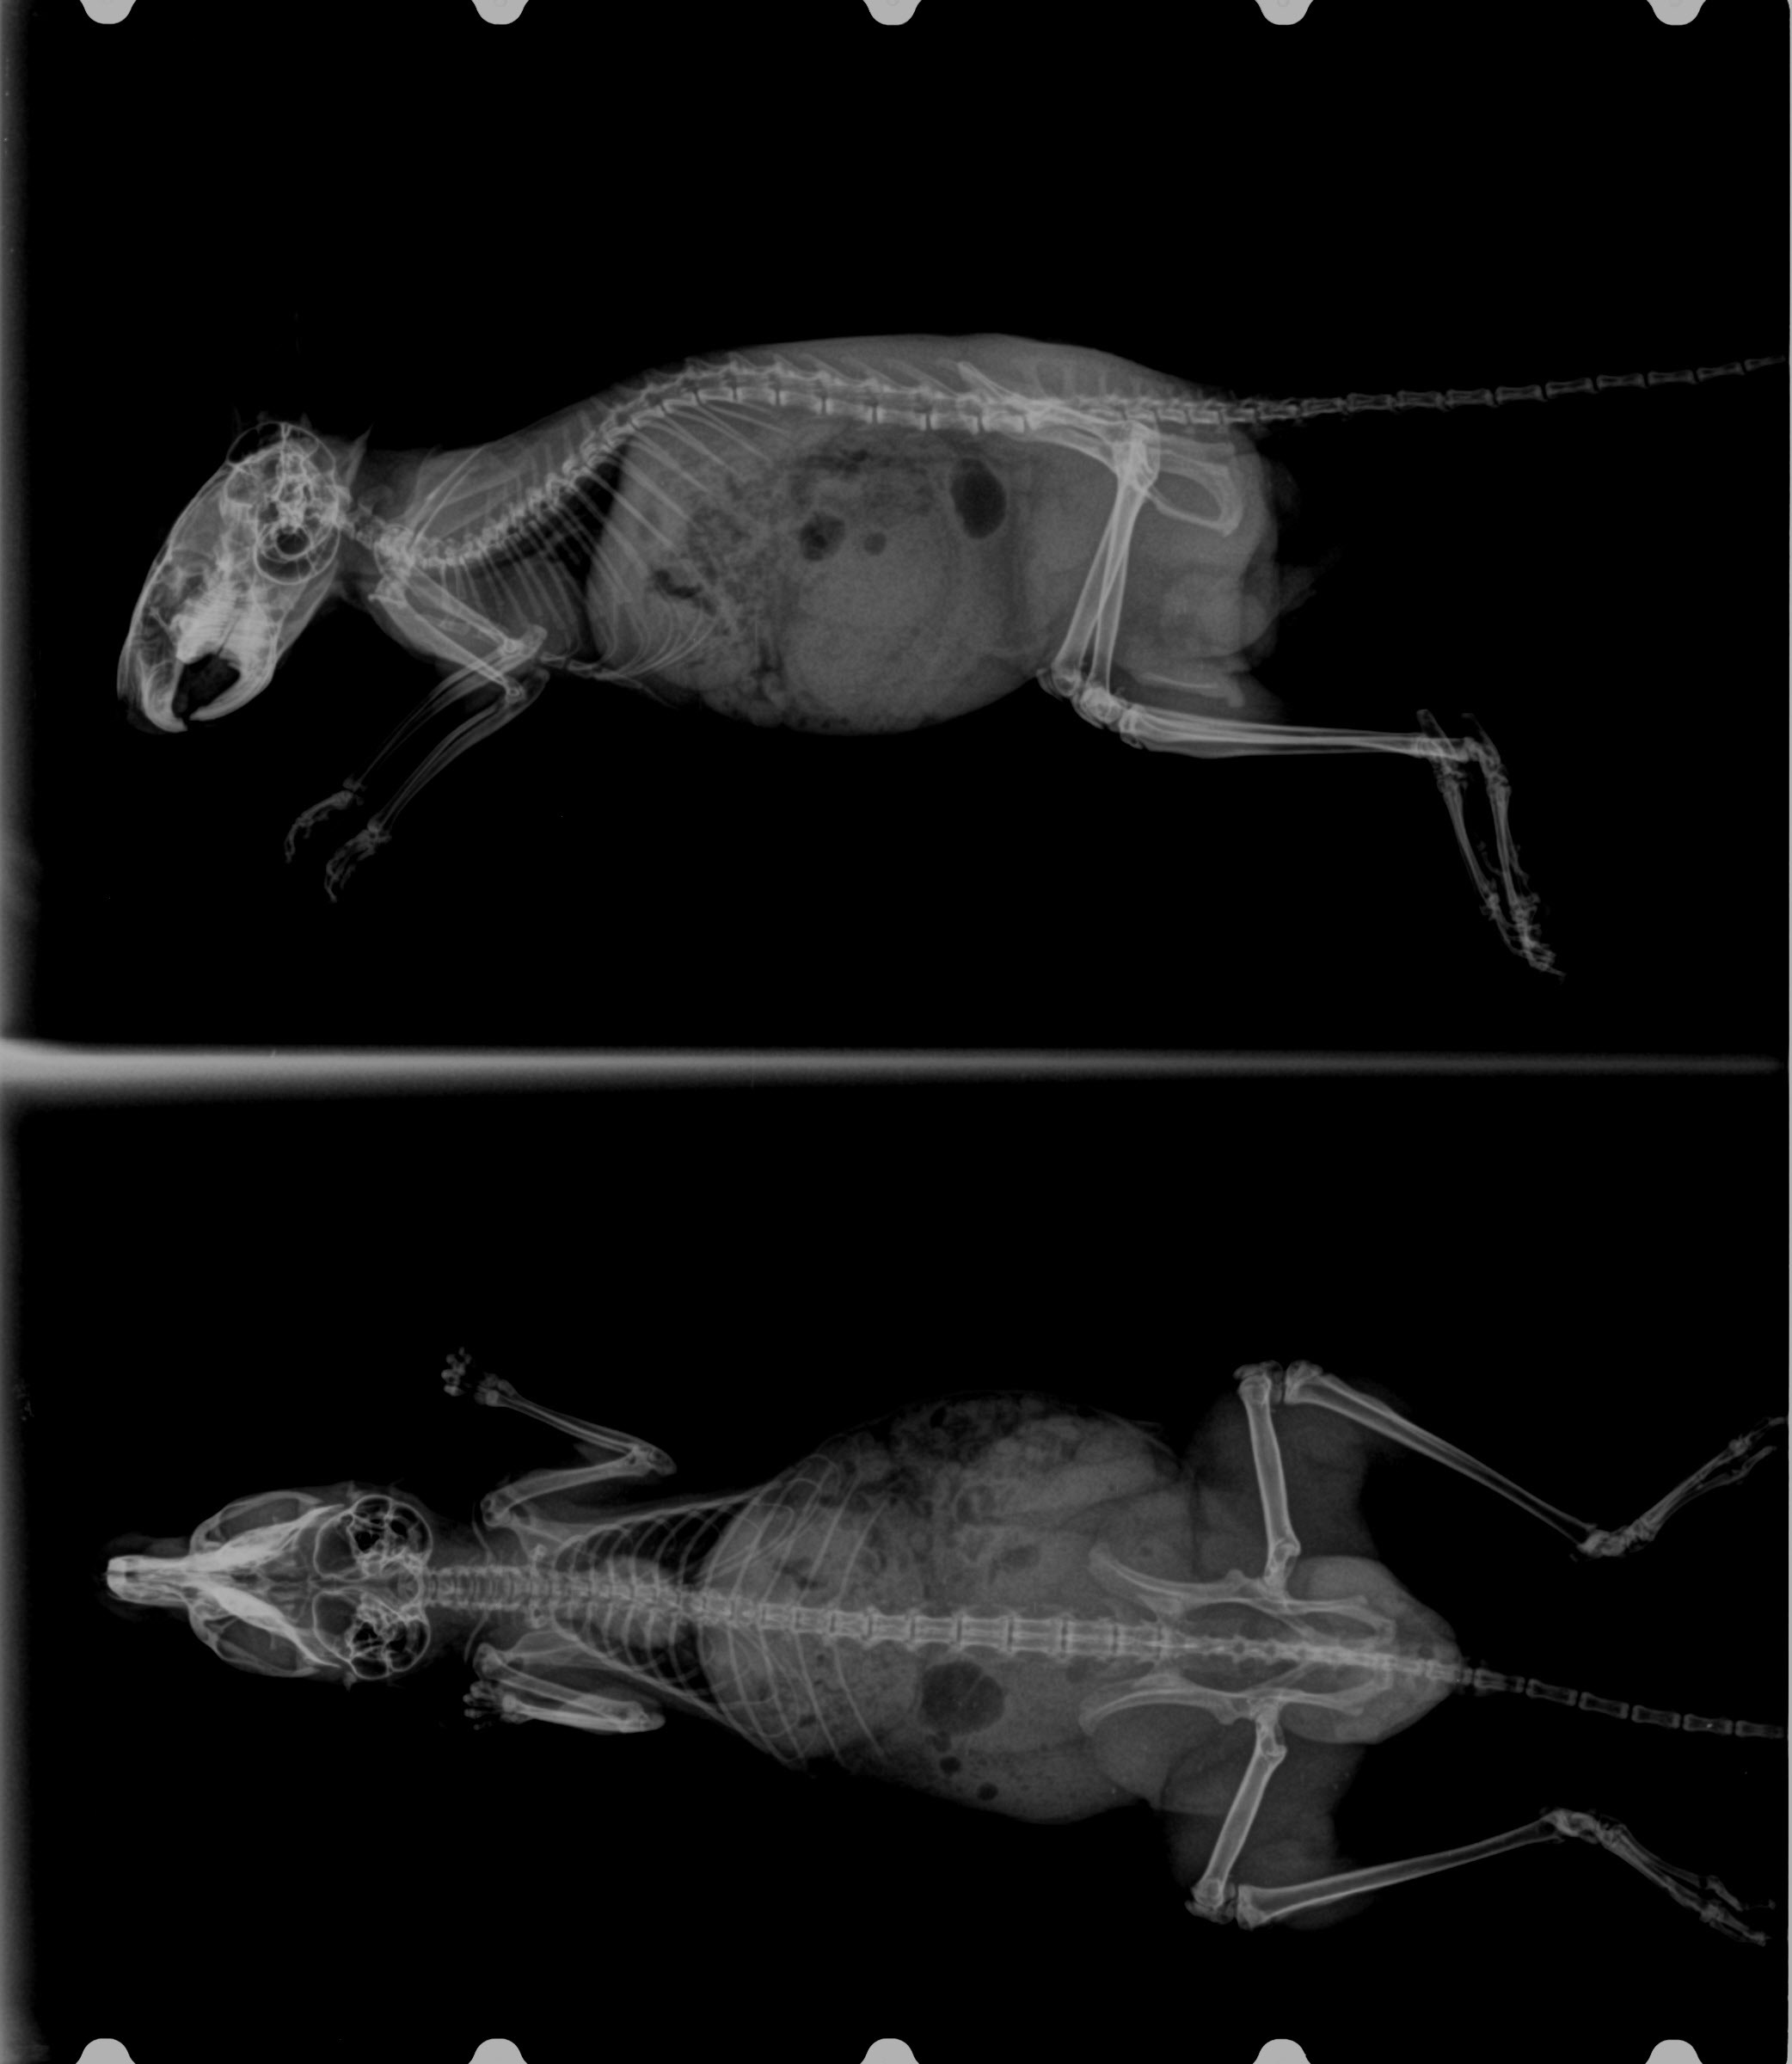

Интересные снимки скелета дегу и его особенности

Раздел: Другие животные